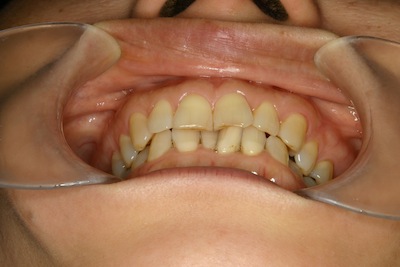

大人の矯正 adult orthodontic treatment

こんにちは さいたま市なると歯科院長の小林成人です

大人の矯正の治療例

子供のうちしか矯正はできませんかと問い合わせをよくいただきます

何歳でも矯正は可能です

80歳でもちゃんと歯は動きます

但し、子供と比べて動くスピードが遅いので、治療期間が長めになる傾向が

ありますので、できれば子供のうちにやっておいた方がらくだとおもいます

上下の前歯がねじれているのを気にされて来院されました

正面から見るとそれほどでもないように見えますが

下から覗くと結構ねじれています

見た目の問題だけではなく、磨きにくく歯石も貯まりやすいので

虫歯や歯周病にもなりやすい状態です

抜歯して被せる方法もありますが

今回はできるだけ抜かずに部分矯正で対応する事にしました

上の前歯2本がねじれています

下の前歯も窮屈そうです

ストリッピングテクニックで少しずつ歯を並べていきます

矯正終了時

綺麗に並びました

横から見ても綺麗です

これでかなり磨きやすくなり、食べカスもつまりにくくなりました

上顎

下顎

共に綺麗に並びました

裏側は後戻り防止装置のワイヤー固定をしてあります

治療期間 約1年

お疲れさまでした